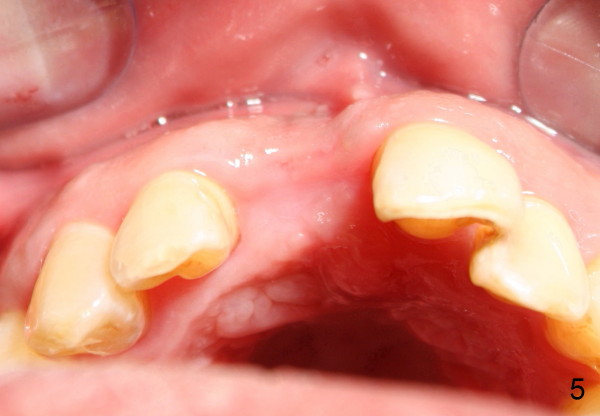

Two months after socket debridement, the wound appears to have healed with mild to moderate buccal plate atrophy (Fig.5).  Bone height is ~ 21 mm (Fig.6).  D2 short or long implant is planned.  Is this appropriate?